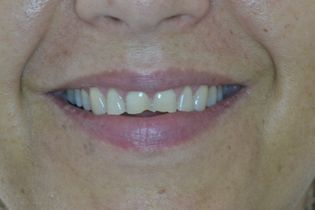

Η νεαρή αυτή ασθενής προσήλθε στο ιατρείο παραπονούμενη για την εμφάνιση των τεσσάρων άνω τομέων της.

Τα δόντια είχαν με την πάροδο των ετών σπάσει στην κοπτική τους επιφάνεια και το φαινόμενο αυτό επιδεινώνονταν σταδιακά με απώλεια όλο και περισσότερης οδοντικής ουσίας.

Αποφασίστηκε να αποκατασταθεί η δομική ακεραιότητα των δοντιών αυτών με χρήση σύνθετης ρητίνης νανουβριδικής τεχνολογίας (Herculite XVR Ultra/Kerr).

Η αποκατάσταση τους έγινε σε ένα ραντεβού και το αισθητικό αποτέλεσμα ικανοποίησε στο ακέραιο τις προσδοκίες της ασθενούς μας.